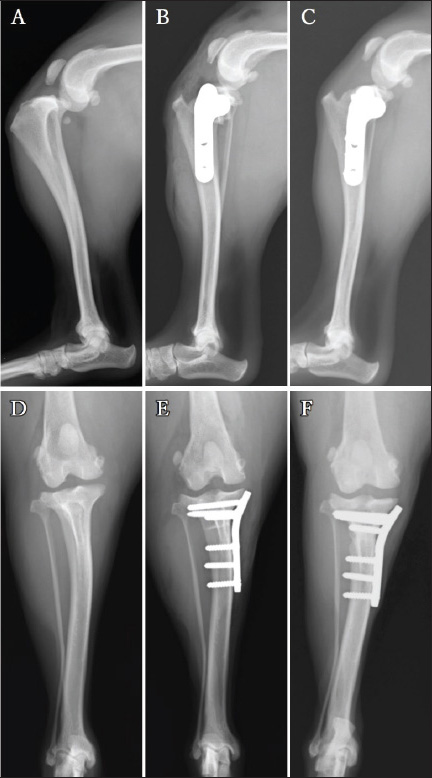

Radiography of the right stifle joint indicated infrapatellar fat pad signs and cranial tibial luxation (Fig. 1A). No obvious angular limb deformities were observed (Fig. 1A and D). Ultrasonography of the stifle joints (ARIETTA Prologue; Fujifilm Co., Japan; 18 MHz linear probe) revealed a complete CCLR, severe joint effusion, and medial buttress in the right stifle joint with no injury to the medial meniscus (Fig. 2A–C). Furthermore, partial CCLR and mild joint effusion were observed in the left stifle joint.

During the tibial compression test post-TPLO plate placement, tibial cranial subluxation and internal rotation occurred intraoperatively. An LFTS was placed using a No. 3 monofilament nylon and an LFTS needle (BEAR Medic Co., Japan) as follows: a single strand of LFTS was passed around the lateral femoral fabella, cut at the needle, and both ends passed under the patellar ligament. One end of the strand was then passed proximally to the cranial screw under the TPLO plate, and the other end was passed distally through the same screw (Fig. 3A). The surgeon’s knot was ligated to the caudal side of the TPLO plate (Fig. 3B). The resolution of the tibial dislocation was confirmed with a second tibial compression test. The incision was closed in three layers, and two orthogonal postoperative radiographs were acquired to evaluate the position of the implants and bone fragments. A modified Robert Jones bandage (soft padded bandage) was applied under general anesthesia after postoperative radiography (Fig. 1B and E) and maintained for 2 days. The non-steroidal anti-inflammatory agent firocoxib (Previcox®; Boehringer Ingelheim Animal Health Japan Co., Ltd., Japan) was administered orally at 5 mg/kg every 24 hours, and cefazolin (Cefaclear®; Kyoritsu Seiyaku Co., Japan K.K., Japan) at 20 mg/kg every 12 hours for 5 days postoperatively. Lameness evaluation, client satisfaction, and radiographic follow-up were performed at 10 days and 4, 8, and 14 weeks postoperatively.

Fig. 1. Mediolateral radiographs (A–C) and caudocranial radiographs (D–F) of the right limb. The infrapatellar fat pad sign and cranial tibial luxation at the first visit (A). Absence of angular limb deformities (D). Placement of a 2.4-mm TPLO plate (B and E). No osteotomy line at the 14-week follow-up (C). No evidence of dislocation at the 14-week post-TPLO (F) follow-up.

Postoperative radiography revealed that the TPA was 5° on both sides. The owner was satisfied with the postoperative weight-bearing ability of the limb while walking at the 4-week follow-up visit. A faint osteotomy line was visible, and radiography revealed aligned and positioned TPLO plates and bone segments with no displacement. No tibial translocation was detected during the compression test. The dog was able to use its right hind limb without any discomfort at the 8-week follow-up visit. The osteotomy line had disappeared, and radiography revealed aligned TPLO implants. Tibial translocation was not detected during the compression test. Minimal discomfort upon waking up was reported at the 14-week follow-up visit for the right limb (4-week follow-up for the left limb); lameness was not observed while walking or trotting. The tibial compression test results were negative for both limbs, and the rotated bone fragment showed complete fusion with the tibia of the right limb (Fig. 1C and F). A faint osteotomy line was observed in the tibia of the left limb. Radiography revealed no dislocation of the bone or the TPLO implants on the right or left sides. The owner was pleased with the significant improvement in walking ability. By the 13-week follow-up visit osteotomy line in the left limb was not visible, with no residual discomfort or lameness in either limb. The osteotomy line was not apparent owing to bone union (Fig. 4C). The implant alignment and bones remained stable (Fig. 4F).

Fig. 4. Mediolateral radiographs (A–C) and caudocranial radiographs (D–F) of the left limb. The infrapatellar fat pad sign and cranial tibial luxation at the left stifle joint before the surgery (A). No obvious angular limb deformity can be visualized (D). A postoperative radiograph acquired after the 2.4-mm TPLO plate placement (B and E). The tibial bone and bone fragment are completely fused at 13 weeks post-surgery (C). Additionally, the caudocranial radiograph at the 13-week (F). Follow-up visit shows no sign of dislocation of the implants.